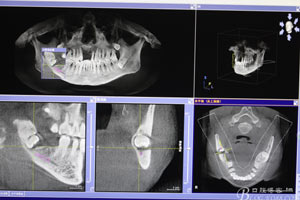

圖4.總體的CBCT影像: